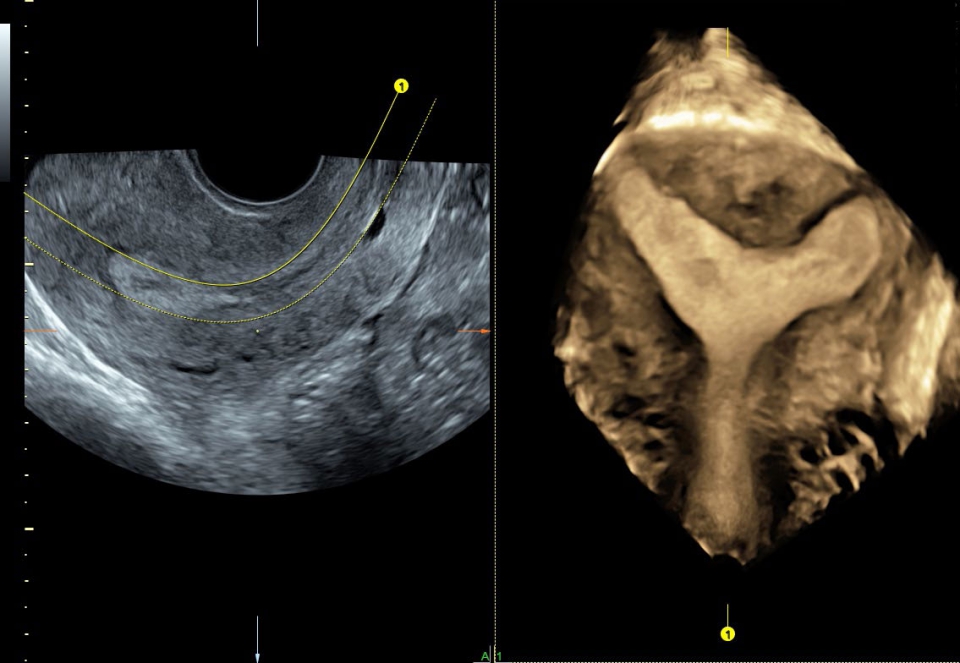

• SonoRenderlive (Автоматическое объемное изображение): Эта функция упрощает получение объемного изображения путем автоматического выбора положения плоскости визуализации для 3D- и 4D-режимов. Это сокращает необходимость вручную настраивать параметры и упрощает процесс получения объемных изображений.

• Расширенный программный пакет объемного контрастного изображения (VCI) для объемных датчиков

• SonoNT (Оценка воротникового пространства) и SonoIT (Оценка внутричерепного пространства): Эти технологии позволяют проводить полуавтоматическую оценку толщины воротникового пространства и размеров IV желудочка головного мозга плода в I триместре беременности. Они обеспечивают более точную оценку этих параметров с минимальными усилиями.

• SonoAVC (Автоматический расчет объема): Эта функция позволяет визуализировать и рассчитывать размеры и объем гипоэхогенных образований, таких как фолликулы яичника или структуры головного мозга плода. Она помогает в оценке этих образований и отслеживании их изменений в течение времени.